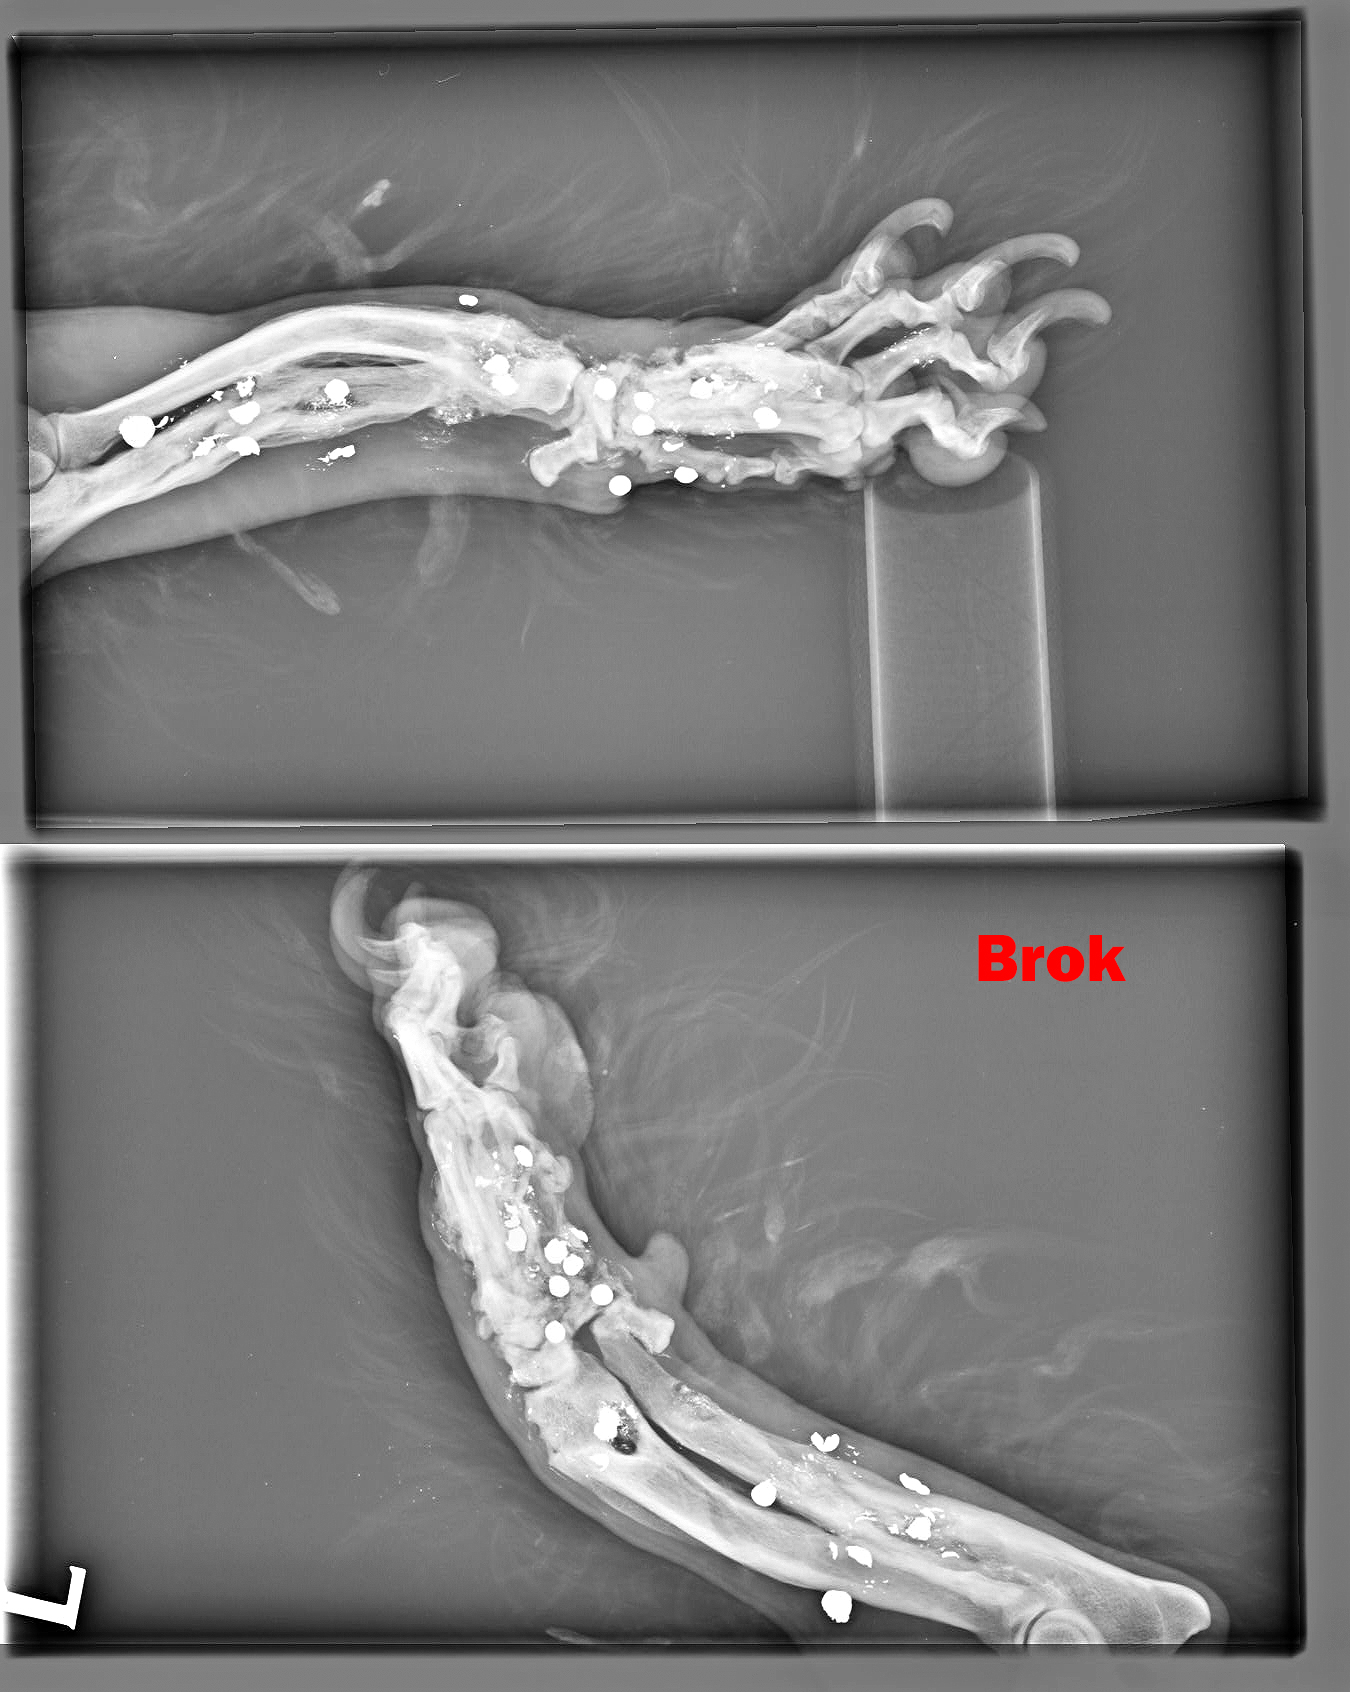

BROK - dostal meno Brok, keďže sa stal živým terčom a má vo svojom malom telíčku nespočetné množstvo brokov. Labka je vykrivená preto, že sa mu v dôsledku streľby dolámali kosti...

Image removed.BROK - dostal meno Brok, keďže sa stal živým terčom a má vo svojom malom telíčku nespočetné množstvo brokov. Jeho brata sme odchytili pár mesiacov pred ním, keď do neho deti hádzali petardy. On z toho vyviazol bez problémov, ale žiaľ Brok to šťastie už nemal. Jeho celá nožička je zdeformovaná, dostieľaná, dolámaná. On nenatrafil na deti, ale na dospelého, zjavne psychicky narušeného človeka, ktorý mu neskutočne ublížil. Odpusťte mi, keď do prosby vnesiem aj emócie, ale pri pohľade na neho sa topím v slzách. Brok je jeden z najláskavejších psíkov akého sme kedy mali. Miluje ľudí, objíma ich aj tou boľavou nožičkou. Rozdáva pusinky každému. Má celý život pred sebou. Tak rád by bezstarostne behal a naháňal sa, ale potkne sa aj o vlastnú nohu. Skáče na človeka, akoby sa odprosoval, že už nikdy viac nebude neposlušný, len nech mu už nikto neublíži. Chce dokázať, že je dobrý, že nadovšetko miluje a nechce ho pustiť, už nikdy viac nechce byť bez svojho človeka. Toľko toho ešte môže a musí zažiť! Potrebuje svoju nožičku a musíme mu pomôcť. Bude to nákladné, ale toto je jednoducho situácia, ktorú musíme vyriešiť a dopriať mu plnohodnotný život. Brok má v nešťastí obrovské šťastie. Keď sme si mysleli, že jediným riešením bude amputácia, ujal sa ho najlepší ortopéd v republike, MVDr. Vatolík a nožičku mu vie napraviť. Bročko ale potrebuje Vašu pomoc, lebo bez nej to nepôjde. Diagnostiku a prvú operáciu, odstránenie brokov z tkaniva má už úspešne za sebou. Zatiaľ má "len" malé ranky, z ktorých sa rýchlo zotaví. Momentálne čakáme na výsledky kultivácie. Tkanivo musí byť "čisté" bez akejkoľvek infekcie, bez akýchkoľvek baktérií, aby sa mohlo ďalej pokračovať.

Labka je vykrivená preto, že sa mu v dôsledku streľby dolámali kosti a keď sme ho našli, už bolo všetko zahojené a zle zrastené. Za diagnostiku a prvý zákrok máme faktúru vo výške 449,23€.

Ďalšia operácia, ktorá ho čaká 21.5.2020 bude ale veľmi náročná. Treba odstrániť broky z kostí, a tým pádom bude treba vyrezať časť zlomených a zle zahojených kostí v nožičke. Tieto časti sa následne nahradia implantátmi (pán doktor ešte zvažuje či použiť implantáty z titánu, ktoré sú prijateľnejšie pre organizmus, alebo implantáty z chirurgickej ocele, ktorá je pevnejšia). Bročko bude mať v nožičke vnútorné fixátory, ktoré ju budú držať pokope, kým sa opäť nezocelí. Nebude to žiadna prechádzka ružovou záhradou, ale zvládneme to! Z našej strany pre neho urobíme všetko a doprajeme mu plnohodnotný a bezstarostný štart do nového života. Potrebujeme ale Vašu pomoc. Náklady na operáciu sa predpokladajú do výšky okolo 1500€. Celkom teda za Bročka cca 2000€.